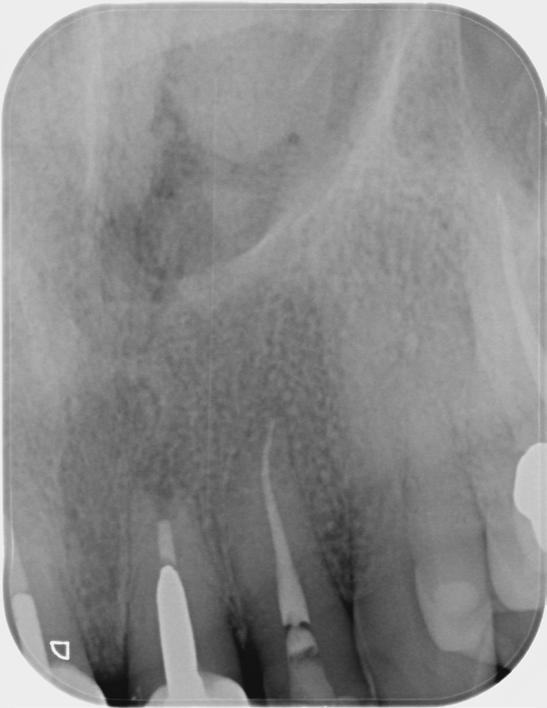

Based on the clinical and radiographic findings, tooth 22 was diagnosed as necrotic with a possibly infected root canal system (RCS), pulp canal calcification and primary acute apical periodontitis due to decay, cracks and restoration breaking down. An endodontic investigation procedure was planned to determine whether the 22 was suitable for further restoration. While the treatment was supposed to be straightforward initially, it progressed to become very complex surprisingly. This was due to separation of a size-10 H-file in the root canal of tooth 22.

The instrument separation was first noticed after taking the initial radiograph to establish the working length. It probably happened due to the patient biting inadvertently on the file during x-ray exposure. As our patient was a bruxer, his bite forced the file deeper in the

severely calcified root canal. The file was now firmly stuck inside the root canal. Despite trying to gently retrieve the file, it broke at junction of the cutting surface to the shank. Bypassing and/or retrieval procedures were planned and performed by using hand files, rotary files and Satelec ultrasonic tips in three different sessions, each one almost three hours long. Rotary files were used mainly as adjunctive instruments.

Taking advantage of rotary files made of a heat-treated alloy with minimal cutting efficiency, designed in a way to scrape rather than cut the dentin, enabled me to safely enlarge the space made by the hand files. This technique also participated in less frequency and chance of breaking more files next to the broken file.

Finally, the broken file segment was removed with braiding barbed broaches around the file. Notably, the patient patiently cooperated all throughout the treatment.

I had a thorough discussion with the patient about the reasons why this incident happened. Even though I could have simply pointed out a severely calcified root canal or a heavy bite to be responsible for the incident, I concluded that the patient’s occlusion should have been assessed carefully during case assessment in order to set preventive measures, which in turn could have potentially saved the patient and I from all the consequences.

Take home message - ALWAYS check your patient’s occlusion during the first examination/ consultation session. It will save you a lot of money!

Fig.1 File got stuck (22/09/2023) Fig.2 File fractured (22/09/2023)

Fig.4 Cut the file deeper (22/09/2023)

Bypassed to WL (12/10/2023)

And even deeper (12/10/2023)

Fig.3 Made space coronally (22/09/2023)

Fig.6 Rotary files used (12/10/2023)

Fig.8 Finally retrieved the file (12/10/2023)